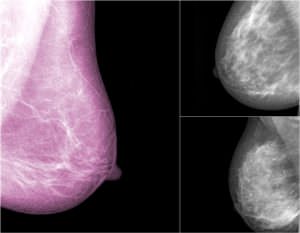

• Une mammographie est une radiographie des seins qui permet de détecter un cancer du sein

mammographie de dépistage

Il est recommandé tous les deux ans et consiste à réaliser une mammographie et à pratiquer un examen clinique des seins.